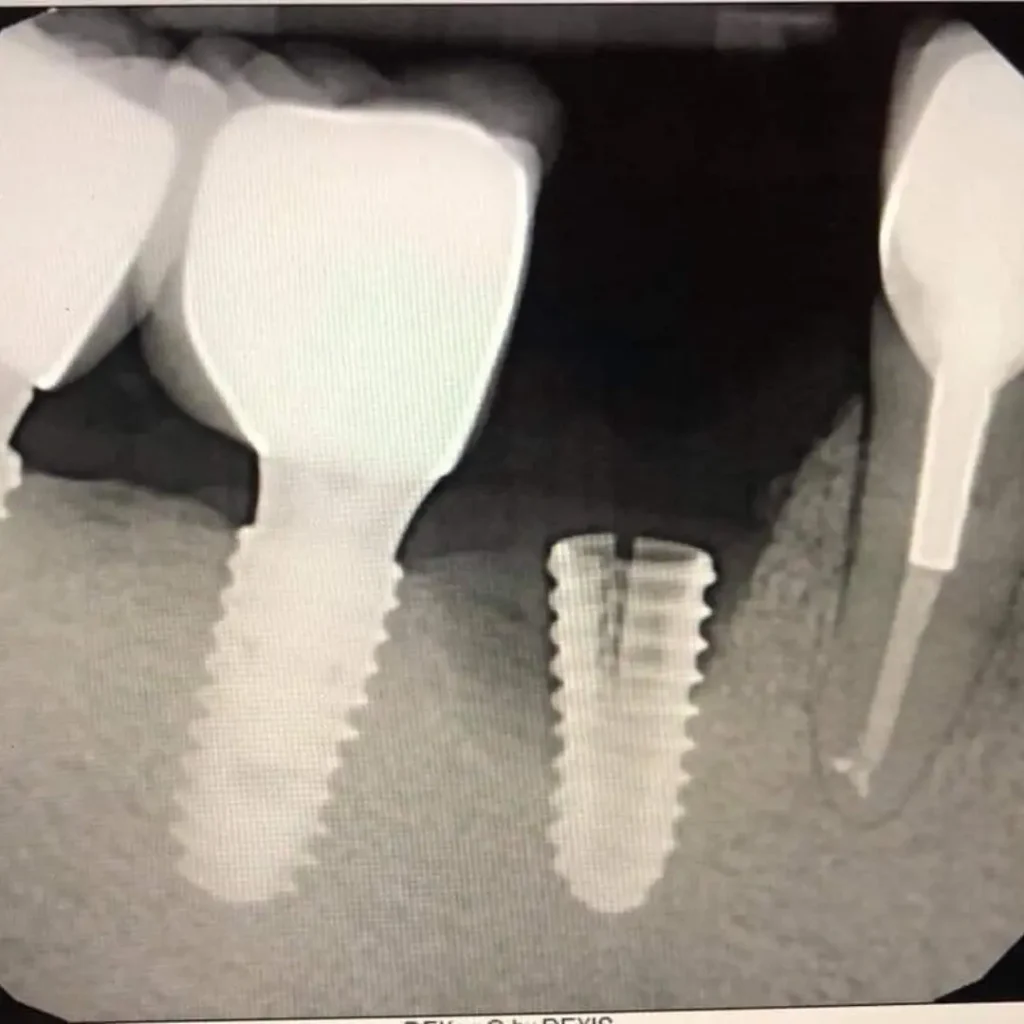

- Advanced Technology - for fast, accurate diagnostics and implant repairs

A dental implant emergency includes a loose dental implant, pain or swelling around the implant, a broken crown, or sudden implant failure due to trauma or infection. If left untreated, these issues may affect surrounding soft tissue, bone, or even your overall health, so prompt emergency dental care is crucial.

Yes. Gum disease (also called peri-implantitis when around an implant) can compromise the success of your dental implant by damaging the surrounding soft tissue and bone. Early detection and treatment are key to saving the implant.

In cases where there’s bone loss, a bone graft may be required to rebuild the area before the dental implant procedure. Our specialists will evaluate your condition and develop a personalized treatment plan.

Yes. Depending on the issue, we may repair the implant restoration, replace the artificial tooth root, or adjust the surrounding crown or abutment. Our emergency dental services ensure quick, effective care to restore your implant.